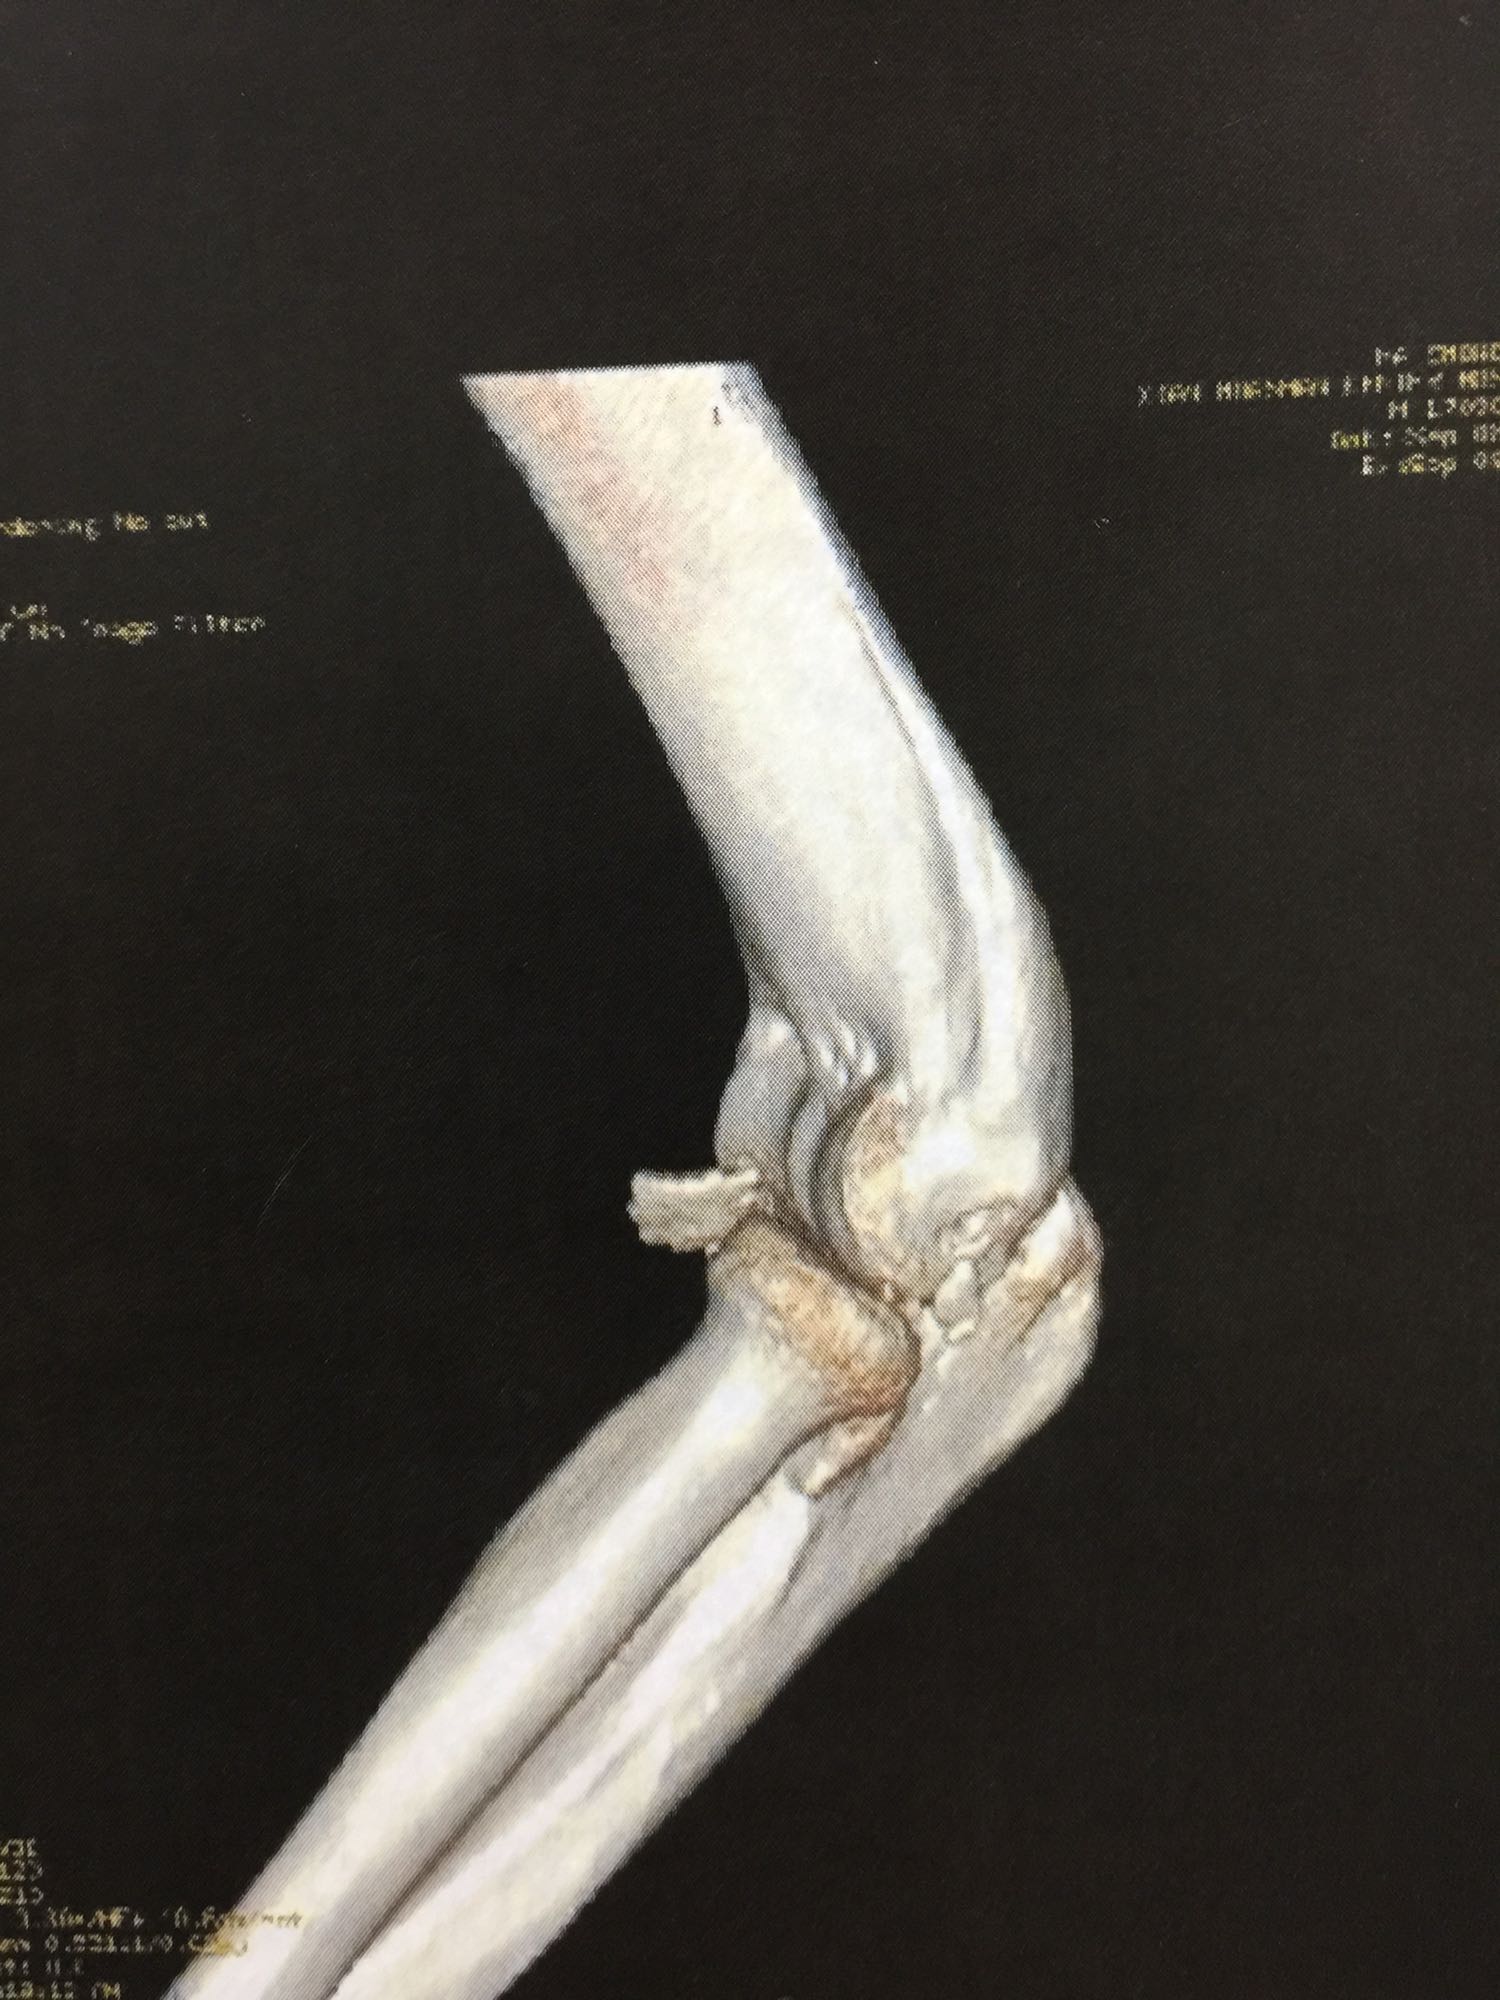

左肘关节高度肿胀,压痛强阳性,肘关节明显活动受限,末梢血运良好,各指关节运动正常。 X线片及CT如图:

1、左尺骨冠状突骨折;2、左肱骨外髁撕脱骨折 治疗:入院后伤肢石膏外固定,给予局部冷敷消肿治疗,于伤后一周行骨折手术治疗,先行前内侧切口复位固定冠状突骨折,活动肘关节发现关节明显不稳定,随取外侧切口,复位固定肱骨外髁,修补外侧副韧带,肘关节明显稳定。术中术后片子如下